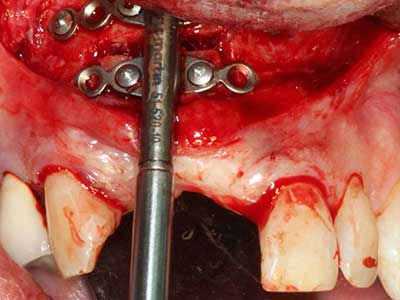

Фиг. 27: 21-годишен пациент след превръщаща остеотомия с персистираща ретрогнатия с клас II дисгнатия.

Фиг. 28: По време на отстраняване на метал, базалните зони на брадичката са разделени с Piezomed при запазване на кръвоснабдяването.

Фиг. 29: Преместване на брадичката напред с 5 mm и фиксация с две пластини за остеосинтез (KLS Martin). Двата нерва могат да бъдат открити в маргиналната област.

Фиг. 30: Естетическото подобряване на контура на брадичката може да се види ясно след операцията.